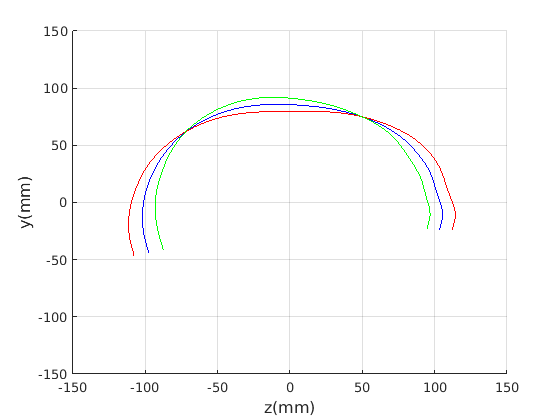

Figure 16 shows examples of the robust ellipse fit for four head profiles. The centre of the ellipse is used in a pose normalisation procedure where the ellipse centre is used as the origin of the profile and the angle from the ellipse centre to the nasion is fixed at -10 degrees. We call this Ellipse Centre - Nasion (ECN) pose normalisation and later compare this to GPA. The major and minor axes of the extracted ellipses are plotted as red and green lines respectively in Fig. 16.

|

Figure 17 shows all 100 profiles overlaid with the same alignment scheme. The median value of major ellipse axis and the ellipse centre-nasion angle differ by 3.6 degrees, so that when the nasion angle is fixed at -10 degrees, the median ellipse angle is -6.4 degrees (cf. -7.4 degrees with manual landmarking of the nasion). We noted regularity in the orientation of the fitted ellipse as is indicated by the clustering of the major (red) and minor (green) axes in Fig. 17 and the histogram of ellipse orientations in Fig. 18. For most people, the major axis of the ellipse is closely aligned with the y-axis (upright), and titled slightly forwards. A minority of heads (9%) in the training sample have their major ellipse axes closer to the vertical (these relatively tall and short heads are known as brachycephalic.) Ellipse axis clustering (relative to the fixed ellipse centre-nasion line) does not appear to be sharply defined. This is because many crania are close to circular in cross-section, making the orientation of these angles sensitive to small changes in shape from one person to the next. Note also the variation at the back of the head due to a variety of hair styles, some of which protrude from under the cap. We limit the region over which we model the cranial shape in order to crop this unwanted data out.